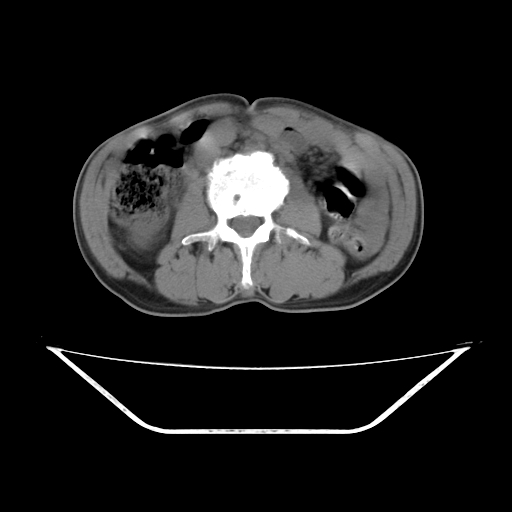

增强

考虑右肾盂癌,肾动脉受侵,右肾功能减退,右肾盂输尿管积水,管壁增厚,考虑种植转移,应该把下面扫完的

考虑右侧肾盂癌。右侧输尿管扩张未扫描完。

右肾盂癌,肾动脉受侵,右肾盂输尿管积水,管壁增厚,考虑种植转移

右肾盂移行细胞癌并右输尿管中段转移.肾积水.

1.右侧肾盂癌伴肾盂积水。

2.肾脏功能减退,原因有:(1)肾动脉受侵。(2)肾静脉受侵(3)肾积水,等。本例,肾动脉显影较好,但受压明显;肾静脉无明显显示,受压或静脉癌栓,下腔静脉腔内未见明显充盈缺损。

3.右侧上段输尿管扩张,原因:(1)积水所致;(2)种植。